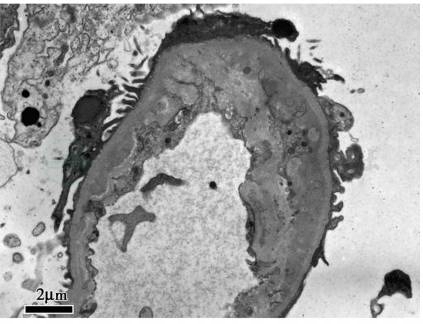

肾穿刺病理学检查(入院第7天):免疫荧光:均阴性。光镜:17个肾小球,肾小球系膜细胞和内皮细胞弥漫增生,基底膜节段性增厚伴假双轨征形成(图1),1个纤维性新月体形成;肾小管上皮细胞空泡及颗粒变性,多灶状及片状萎缩,多数红细胞管型,灶状再生;肾间质弥漫水肿,灶状淋巴和单核细胞及白细胞浸润;小动脉管壁增厚,内皮细胞肿胀;符合血栓性微血管病伴急性肾小管间质肾病。电镜:肾小球内皮细胞节段性增生,基底膜内疏松层增宽,上皮足突大部分融合(图2)。病理结果符合TMA肾损害合并急性肾小管间质肾病。

图2 妊娠相关血栓性微血管病:肾小球毛细血管基底膜内疏松层增厚(电镜×5 000)